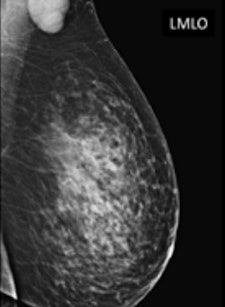

A 65-year-old patient presented with a recent history of a new lump in the left axilla. Clinical examination confirmed a discrete hard palpable mass in the left axilla, in keeping with suspicious finding without clinical breast abnormalities. Mammography and ultrasound were required. Corresponding to the palpable lump, on left mammogram (top) is a rounded mass without any breast lesions, and on ultrasound (bottom) a hypoechoic lesion with no hilum, in keeping with malignant metastatic lymph node. All images courtesy of Dr. Pietro Panizza.